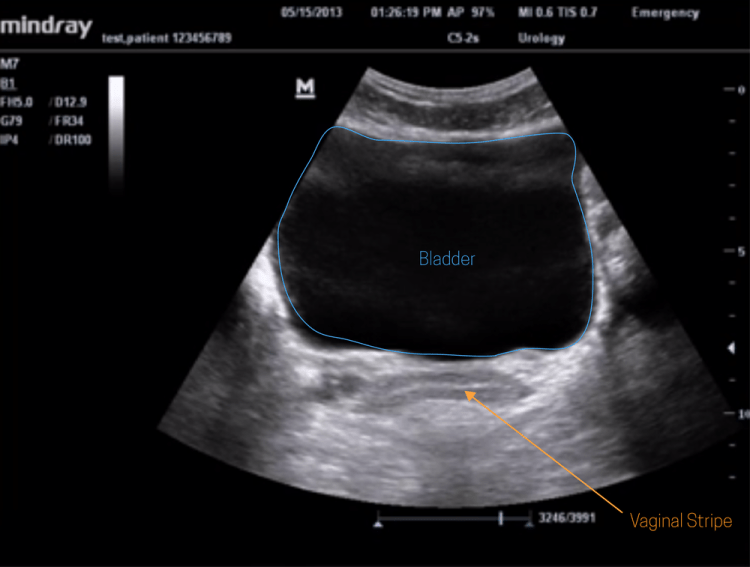

El ultrasonido hepatobiliar permite una visualización detallada del hígado, lo que permite a los médicos identificar anomalías hepáticas asociadas con enfermedades autoinmunes, como la hepatitis autoinmune, la colangitis esclerosante primaria y la cirrosis biliar primaria. Esta capacidad de visualización es fundamental para un diagnóstico preciso y un tratamiento efectivo.